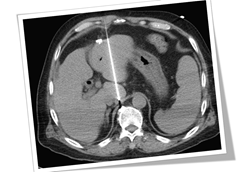

癌王-胰臟癌

2022.06.01

內視鏡超音波 - 早期診斷胰臟癌的利器